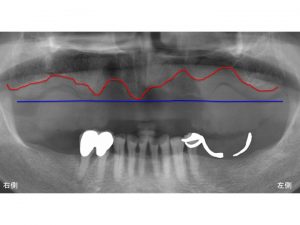

以下が初診時です。

骨吸収を見やすくするために

骨吸収を起こしている現在の状態を赤線で明記します。

赤線まで骨吸収しているため、

骨が凸凹しています。

以下の青線は、骨が吸収前の状態です。

本来は青線まで骨はあったのです。

青線から赤線まで骨が吸収したわけですから

かなり大きいです。